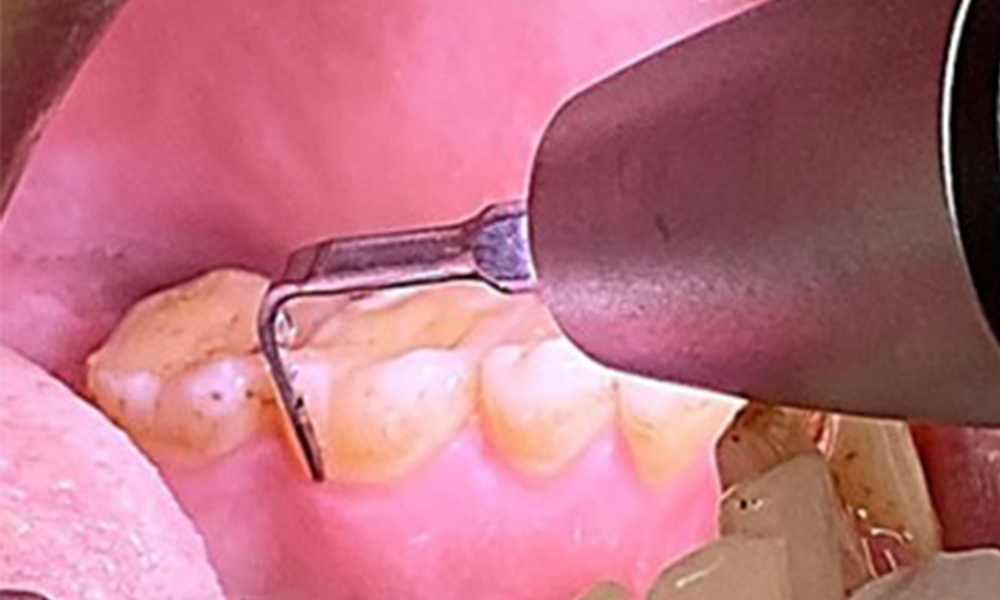

L'objectif serait de contrôler le risque de maladie en éliminant le biofilm supra-gingival et sous-gingival. Les instruments peuvent être sélectionnés en fonction des besoins du patient. Tout d'abord, le tartre et les concrétions doivent être éliminés à l'aide d'instruments ultrasoniques et/ou manuels (Fig. 10).